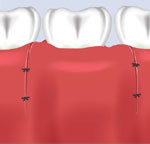

| This transparent view of the gums shows the bone loss that has occurred from periodontal disease. | The periodontist gently opens the area. |

| He then fills it with bone grafting material. | A patch is placed to hold the material in. |

| The periodontist then closes the area and lets it heal. | The bone grafting material will integrate with the bone and the gum will also return to normal. |